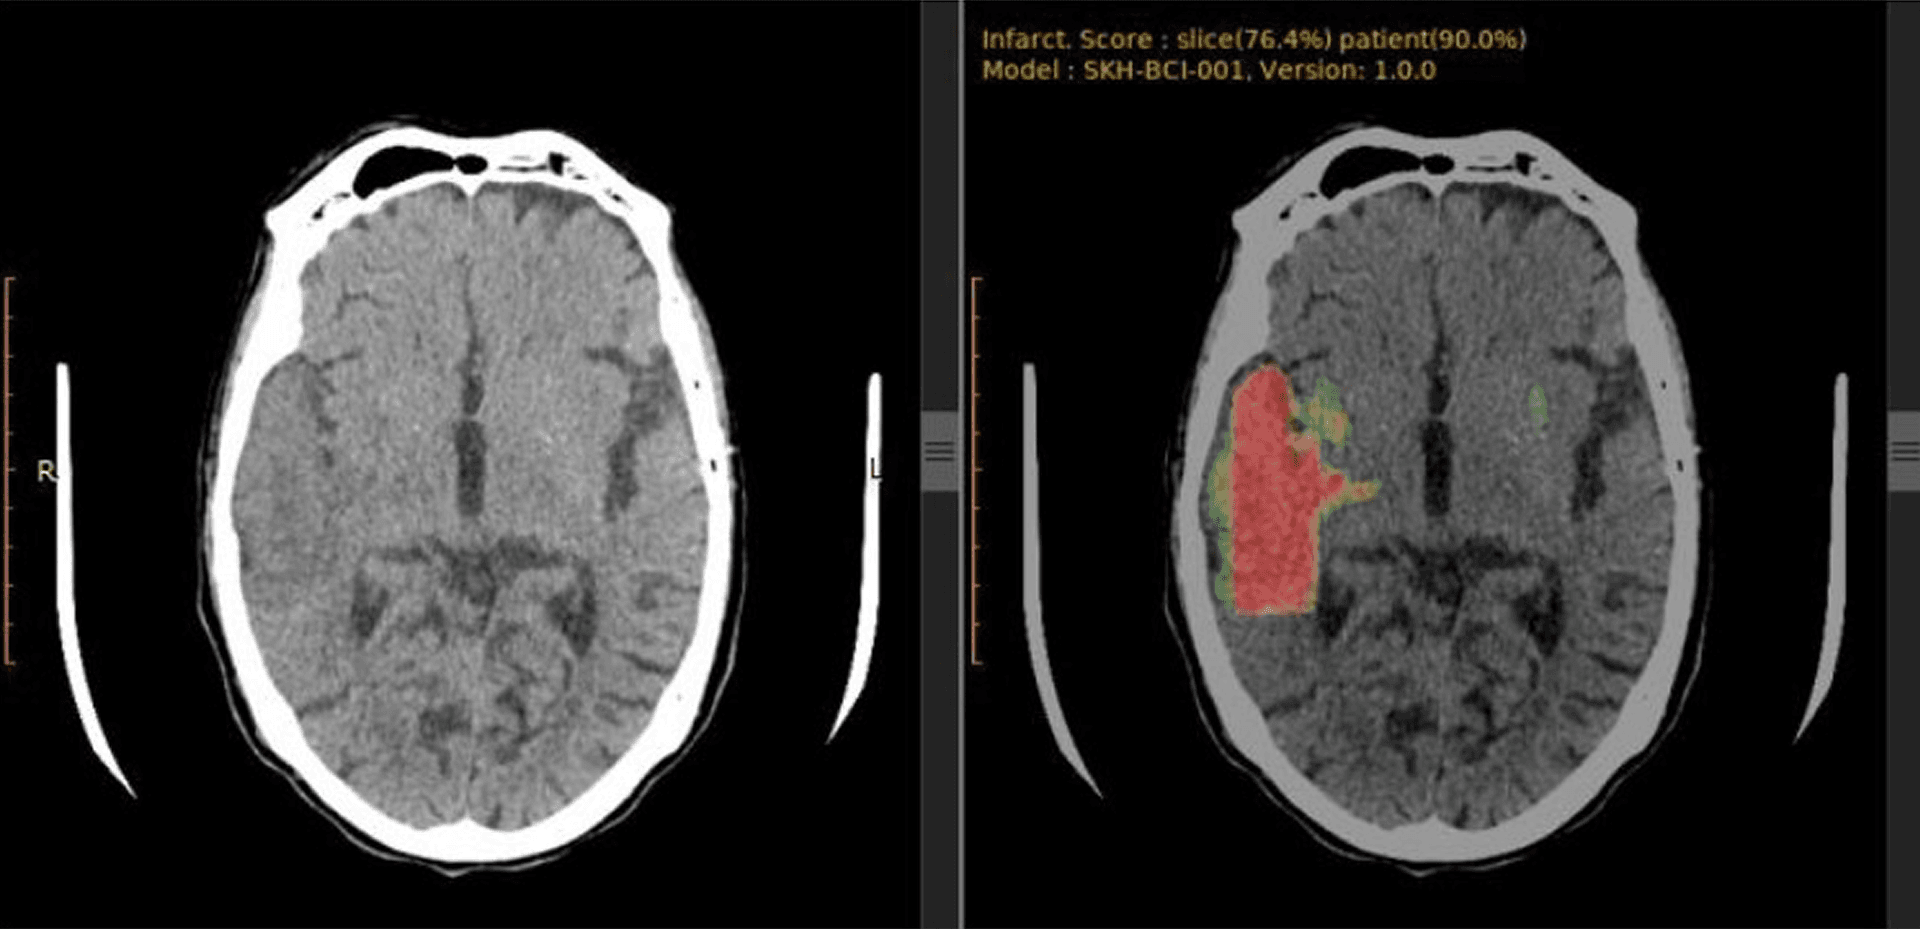

AI clinical decision support (CDS) accelerates physician decision-making, but not all AI is created equal. The most advanced CDS tools go beyond basic detection—precisely identifying, analyzing, and quantifying suspected conditions with exceptional accuracy and speed.